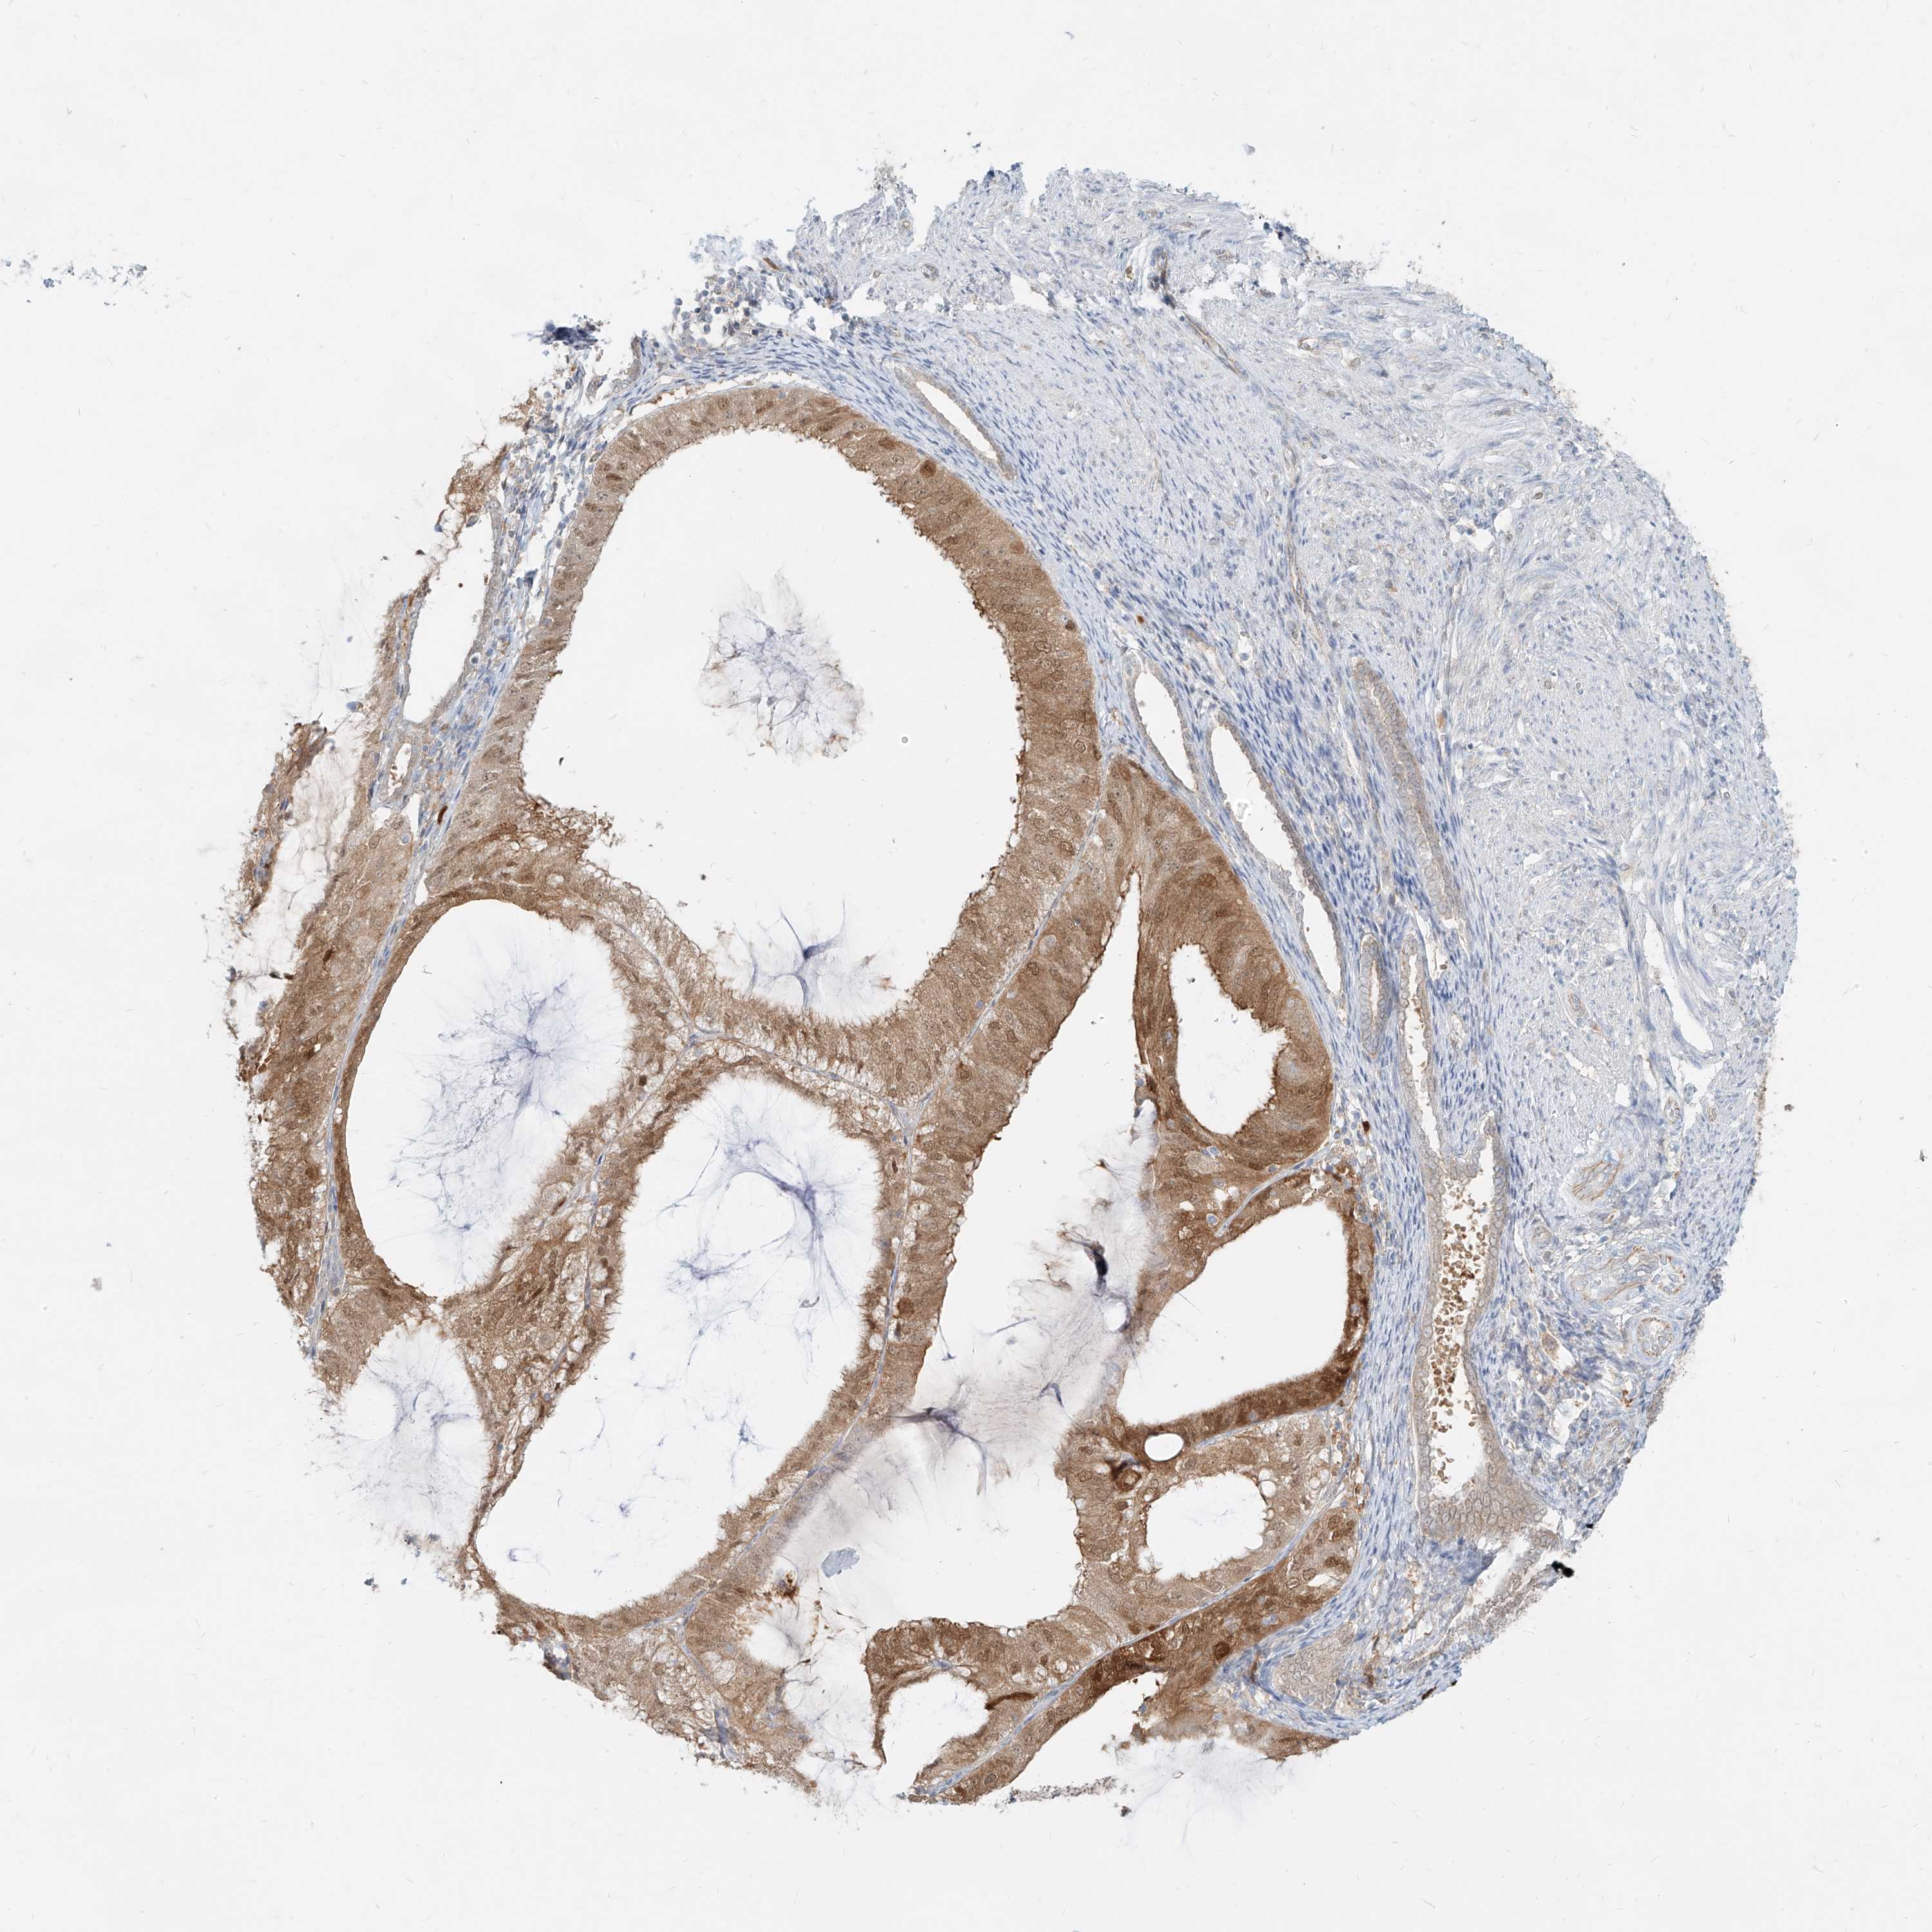

ENDOMETRIAL CANCER - Protein expressioni

A mouse-over function shows sample information and annotation data. Click on an image to view it in a full screen mode. Samples can be filtered based on level of antibody staining by selecting one or several of the following categories: high, medium, low and not detected. The assay and annotation is described here.

Note that samples used for immunohistochemistry by the Human Protein Atlas do not correspond to samples in the TCGA dataset.

Antibody stainingi

Antibody staining in the annotated cell types in the current human tissue is reported as not detected, low, medium, or high, based on conventional immunohistochemistry profiling in selected tissues. This score is based on the combination of the staining intensity and fraction of stained cells.

Each image is clickable and will lead to virtual microscopy that enables deeper exploration of all samples and also displays staining intensity scores, fraction scores and subcellular localization as well as patient and tissue information for each sample.

Antibody HPA031314

Antibody HPA031315

Staining

High

Medium

Low

Not detected

Intensity

Strong

Moderate

Weak

Negative

Quantity

>75%

75%-25%

<25%

None

Location

Nuclear

Cytoplasmic/membranous

Cytoplasmic/membranous,nuclear

Adenocarcinoma, NOS